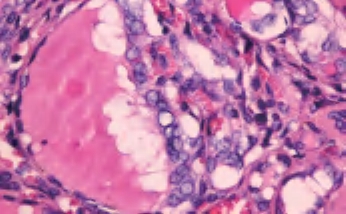

3.镜下 为复杂分支状乳头,含纤维血管轴心,细胞拥挤,核增大,呈卵圆形、沙砾体,表面被以单层柱状上皮,半数以上核呈毛玻璃样,有核沟,核内假包涵体(图3-40至图3-43)。

图3-42 甲状腺乳头状癌,箭头处核内假包涵体